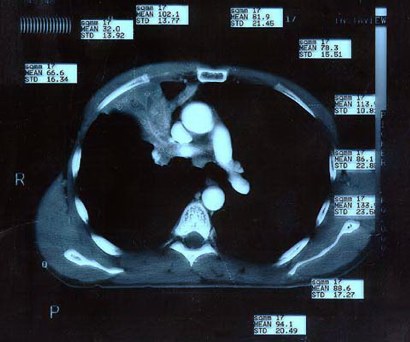

Scan 15th March 1999 No5